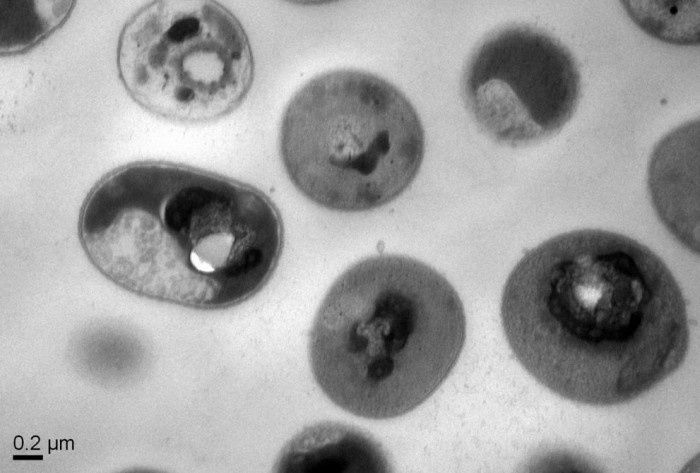

���գ����¼��¿ƌW���g�о���(A*STAR)�Œ����﹤�̺ͼ{�׼��g�о�����IBN���ĿƌW���Լ�IBM�о����ƌW�ҽM�ɵ��о�С�M�ѽ��_�l����һ�N�µĺϳɷ��ӣ����԰���͚�����N�Ͷ�ˎ�������@�N�ϳɾۺ��ﱻ�l�F�ǟo���ģ����ҿ���ʹȫ�µ��ί�������܉��Q������ص��Ϳ����س����������}��

�ϳɷ��ӱ��Q���ҹ��ܻ���̼���������l�F�ȿ����オ���֌����w�����o�������|�ϣ�����늵ĺϳɾۺ����M����w��ͨ�^����΢����Ĥ�����Pؓ늺ɶ��خ��ԽY��ijЩ����������һ���c�����B�ӣ��ۺ��ﴩ�^����Ĥ���|�l�����е����|��DNA�Ĺ̻�������������

ԓ�о�������֮һYi Yan Yang��ʾ�����҂��ѽ��C��������ɽ���ϳɴ���ӵĵ�һ�����ӣ�ԓ�ϳɴ������С���о��ЏV�V�������ԣ����صĚ����C�ƺ͟o���ԡ�һ���ۺ������������乤�����������������Ȼ���Ⲣ�Ҳ��������w�ȣ��@�N��΢������ί����A��������ˎ��ȫ����Ⱦ�@ʾ���ܴ��ϣ������

��С����У��@Щ���ӳɹ�����������������tԺ�аl�F����N��Ҋ����������ԓ�^����С���Л]���@ʾ�����Ե��@���E�󣬲����ڶ��̎���󣬼����]���@ʾ���ۺ���a�����Ե��E��

IBM���о��ˆT�����һֱ�������_�l���и��N�t����;�ĺϳɾۺ������2012�꣬һ���о��F�żȻ�l�F�������Q֮�顰 ���߾ۺ��� ���Ė|�����@Щ�ϳɷ��ӿ��԰���͚��������Ć�ʾ���l��һϵ�������d�^�İl�F��ԓ�F꠷Q֮�顰����ӯ�������

����2016�꣬�҂�չʾ�˺ϳɾۺ�����������������Ĺ�Ч����IBM�о�����James Hedrick��ጵ�����Ŀǰ�ί�������Ⱦ���о�ʹ�҂���������һ�N���͙C���ί�һϵ�Ђ�Ⱦ�������]�еֿ��İl������

��һ�A�ε��о������nj��@�N���g�lչ�ɞ�һ�N����Ŀ����ί�������Ӌ�������w���M���R��ԇ򞣬�������ɞ��ί����w��Ⱦ���·�����